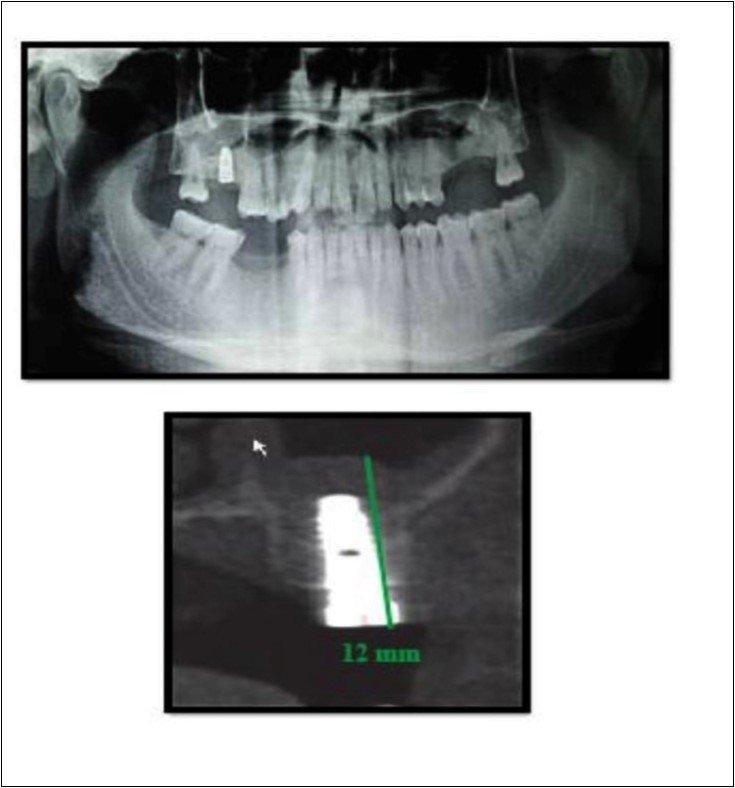

A 75 year old man reported to the unit seeking options for replacement of his missing upper right first molar with fixed prosthesis. Due to the residual bone height of 5.3 mm, the patient was advised and subsequently, underwent the procedure of indirect sinus elevation using sinus osteotomy in relation to 16 region followed by placement of a dental implant measuring 5 mm x 10 mm under local anesthesia and strict aseptic protocols. The implant was allowed to osseo-integrate for a period of six months during which the patient was followed periodically. At the end of 6 months, a CBCT scan showed an increase in bone height to 11.5 mm. (Figure 5)

Figure 5.Pre-operative and post-operative Orthopantomographs and cross sections of CBCT showing residual alveolar bone height